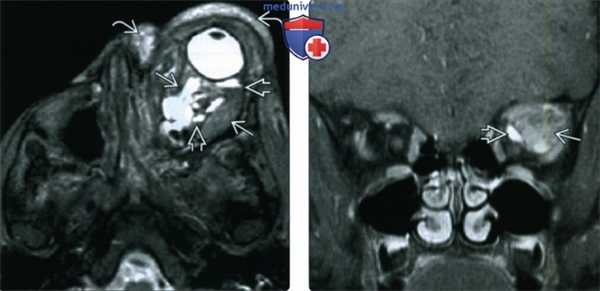

(Слева) При Т2-взвешенной МРТ в аксиальной проекции определяется массивная лимфатическая мальформация сложной формы, вызывающая экзофтальм. Жидкое содержимое, скопившееся в результате неоднократных кровоизлияний, дает вариабельный сигнал и формирует уровни раздела. Также виден еще один, пресептальный, компонент образования.

(Справа) При МРТ Т1ВИ FS с КУ в левой глазнице определяется крупное образование сложной формы, содержащее по большей части неконтрастируемый субстрат, дающий вариабельный Т1-сигнал. Контрастируемая структура с медиальной стороны представляет собой венозный компонента, вероятно, мелкий варикозный узел.

г) Обследование при лимфангиоме глазницы. При КТ выявляется масса мягкотканной плотности с нечеткими границами и негомогенным усилением после введения контрастирующего агента. Деструкция костной ткани отсутствует, но большие новообразования могут вызвать равномерное увеличение глазницы. Наличие кистозного компонента помогает дифференцировать венозно-лимфатические мальформации (лимфангиомы) от периокулярных гемангиом (капиллярных гемангиом) младенцев. Поскольку парамагнитные свойства гемоглобина изменяются при гемолизе, содержащие кровь «шоколадные» кисты хорошо видны при МРТ. Возможно оценить возраст кровоизлияния внутрь опухоли, поскольку гипоинтенсивный на Т1- и Т2-взвешенных томограммах оксигемоглобин при свежем кровоизлиянии постепенно превращается в гиперинтенсивный метгемоглобин.

При дальнейшей деградации метгемоглобина в ферритин и гемосидерин снова получаются гипоинтенсивные изображения. Внутривенное контрастирование при КТ или гадолиниевое усиление при МРТ помогает выявить наиболее активный компонент опухоли, который, если планируется оперативное лечение, должен быть удален. Показано выполнение и анализ томограмм головного мозга на предмет дистантных внутричерепных сосудистых аномалий.

(Б-Г) При МРТ выявлено новообразование в медиальной части глазницы вне мышечной воронки, прорастающее веки и ткани лба и распространяющееся до вершины правой глазницы.

Обратите внимание на кистозный компонент в задних отделах, соответствующий венозно-лимфатической мальформации (лимфангиоме).